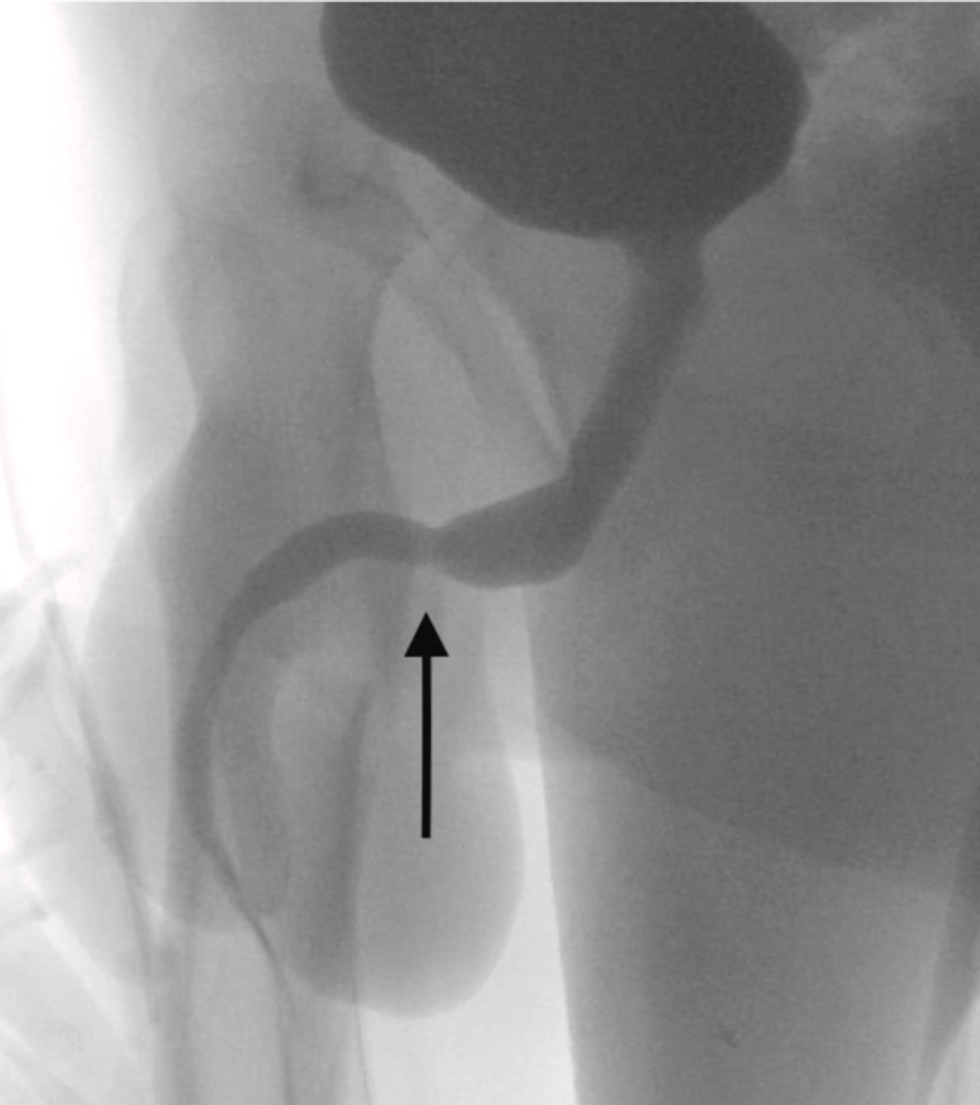

In the report, the doctors wrote: "The two distal ports of the USB wire were found to be protruding from the external urethral meatus whilst the middle part of the knotted wire remained within the urethra. The patient was an otherwise fit and healthy adolescent with no history of mental health disorders."

An attempt to fish the cable out using a metal rod proved unsuccessful to the amount of knotting that had occurred, forcing the team to do surgery on the boy in order to retrieve the cable. They did this by cutting open the section between the genitalia and the anus so they could access the area where the cable was stuck.

In the report, the doctors explain the procedure as follows: "A longitudinal peno-scrotal incision over the palpable foreign body was made and careful dissection was undertaken through deeper tissues, splitting the bulbospongiosus muscle. Both ends of the wire were pulled out successfully through the external urethral meatus."

They add: "Both ends of the wire were pulled out successfully through the external urethral meatus."